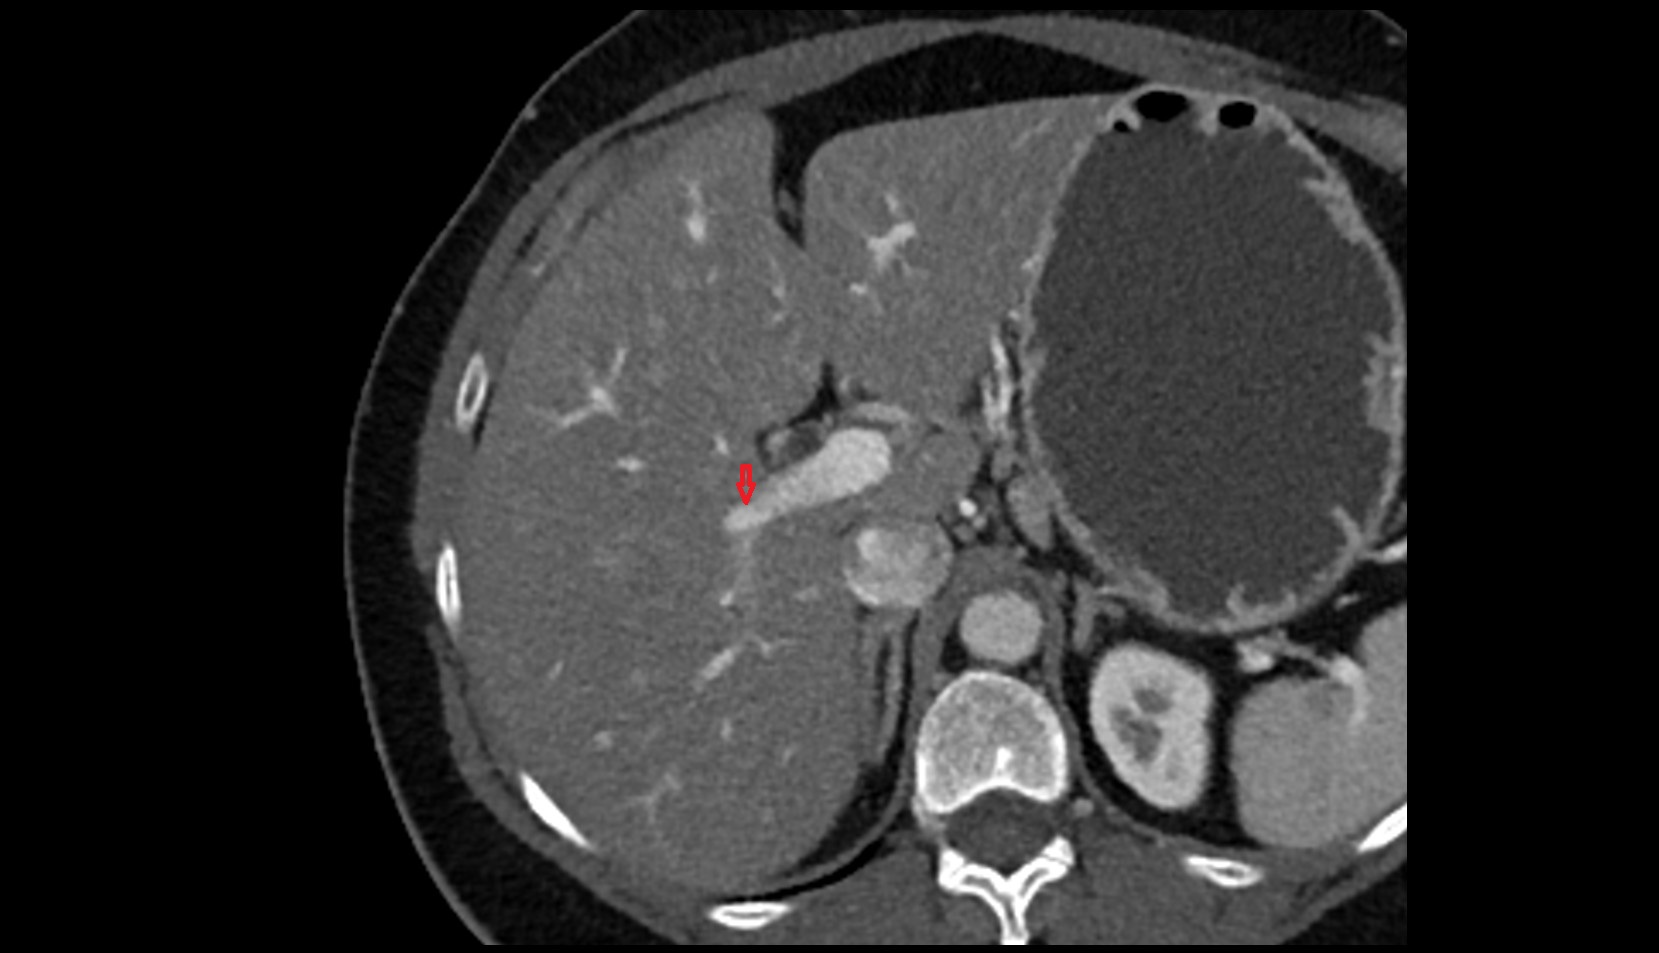

- Right lobe of liver

- Liver

- Liver Segment I – Caudate lobe

- Liver Segment II – Left lateral superior segment

- Liver Segment III – Left lateral inferior segment

- Liver Segment IVa – Left medial superior segment

- Liver Segment IVb – Left medial inferior segment

- Liver Segment V – Right anteroinferior segment

- Liver Segment VI – Right posteroinferior segment

- Liver Segment VII – Right posterosuperior segment

- Liver Segment VIII – Right anterosuperior segment

- Common bile duct

- Common hepatic duct

- Left hepatic duct

- Right hepatic duct